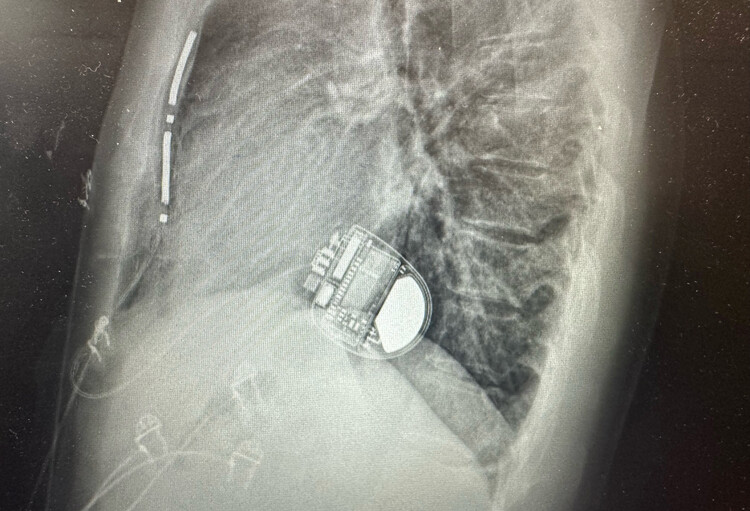

De EV-ICD bestaat uit een defibrillator die onder de linkeroksel van de patiënt wordt geïmplanteerd en geconnecteerd is met een defibrillatie-elektrode die achter het borstbeen voor het hart wordt geplaatst. Het is een extravasculaire defibrillator wat betekent dat er geen elektrodedraden meer door een ader in het hart gebracht worden. Het systeem werkt als een traditionele defibrillator maar elimineert de risico’s die gepaard gaan met het plaatsen van elektroden in het hart. Het laat zowel pijnloze antitachycardie pacing therapie (ATP) als levensreddende defibrillatie toe.

“Omdat we deze nieuwe defibrillator onder de huid aan de zijkant van de borstkas plaatsen, kunnen we de elektrode rechtstreeks achter het borstbeen voor het hart plaatsen," gaat dr. Le Polain de Waroux verder. "Er hoeven dus geen draden in het hart gebracht te worden. Vanuit die positie kan de defibrillator zowel het hart stimuleren als een elektrische schok toedienen. Dit is een nieuwe stap vooruit in de behandeling van patiënten met een ernstige hartaandoening.”